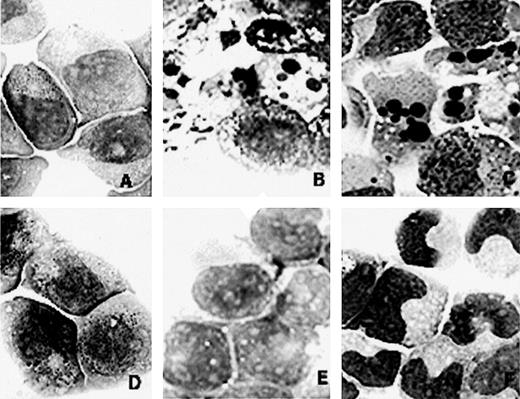

Morphology of NB4 (A, B, and C) and NB4/As (D, E, and F) cell lines on RA or the combination of RA and As2O3 treatment. (A and D) Before treatment. (B and E) After 1 day of treatment with 1 μmol/L As2O3. (C) After 1 day of treatment with 1 μmol/L all-trans RA and 1 μmol/L As2O3. (F) After 4 days of treatment with 1 μmol/L RA and 1 μmol/L As2O3.